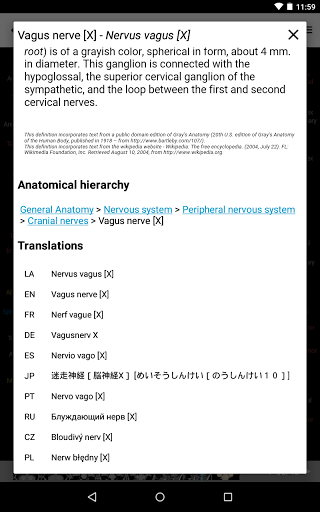

*Browse between anatomical parts using description links

-In the details view of an anatomical structure related terms are now displayed